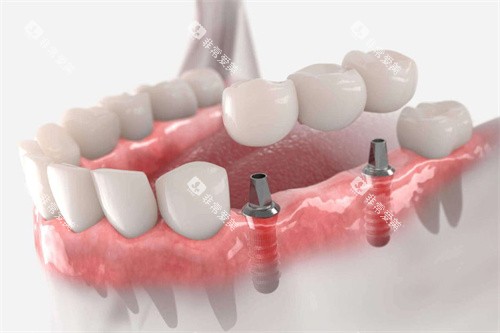

种植牙的结构较好复刻了天然牙的力学特点——植入牙槽骨的种植体相当于“人工牙根”,能与骨骼形成牢固的骨结合,上方的牙冠则替代缺失牙的咬合面。这种结构让咬合力可以直接通过种植体传导至牙槽骨,受力方式与天然牙高度一致。这种功能性刺激能够维持牙槽骨的代谢活性,防止其萎缩。

种植牙的适用范围广泛:单颗牙缺失时,无需磨损邻牙,直接在缺牙位置植入即可;多颗牙连续缺失时,可通过植入少量种植体作为“桥墩”,搭配桥体修复;全口牙缺失时,甚至可以通过4-6颗种植体固定全口牙冠,避免传统全口假牙容易脱落的问题。